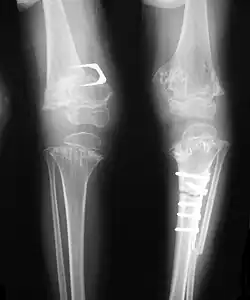

Pseudoachondroplasia. Leg radiographs depicting dysplastic distal femoral and proximal tibial epiphyses, and distal femoral metaphyseal broadening, cupping, irregularities (white arrows) and radiolucent areas especially medially. Note the metaphyseal line of ossification of the proximal tibias (blackarrows) and relative sparing of the tibial shafts. The changes around the knee are known as "rachitic-like changes". Lesions are bilateral and symmetrical.

- Together with rhizomelic limb shortening, the presence of epiphyseal-metaphyseal changes of the long bones is a distinctive radiologic feature of pseudoachondroplasia.

- Metaphyseal broadening, irregularity and metaphyseal line of ossification. These abnormalities that are typically encountered in proximal humerus and around the knees are collectively known as “rachitic-like changes”.

- Radiographic lesions of the appendicular skeleton are typically bilateral and symmetric.